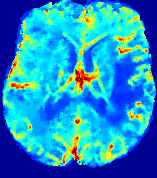

Figure 3: PIANO feature maps for one stroke patient, where the lesion is located in the left hemisphere. Top row: segmented stroke lesion region (white) on different slices, obtained from ISLES 2017. The corresponding slices for the PIANO feature maps are shown in the following rows.

For a better insight into an estimated velocity field 𝐕𝐕{\bf{V}} and diffusion field 𝐃𝐃{\bf{D}}, we compute the following maps: (1) 𝐕rgbsubscript𝐕𝑟𝑔𝑏{\bf{V}}_{rgb}: Color-coded orientation map of 𝐕=(Vx,Vy,Vz)T𝐕superscriptsuperscript𝑉𝑥superscript𝑉𝑦superscript𝑉𝑧𝑇{\bf{V}}=(V^{x},V^{y},V^{z})^{T}, obtained by normalizing 𝐕𝐕{\bf{V}} to unit length and mapping its 3 components to red, green, blue respectively; (2) 𝐕2subscriptnorm𝐕2\|{\bf{V}}\|_{2}: 222 norm of 𝐕𝐕{\bf{V}}; (3) D𝐷D: scalar field in Eq. 5.

Fig. 3 and Fig. 4 show the PIANO feature maps estimated from two ISLES 2017 patients: all are highly consistent with the lesion in both cases. Details of the blood flow trajectories are revealed in 𝐕rgbsubscript𝐕𝑟𝑔𝑏{\bf{V}}_{rgb} by the ridged patterns and the sharp changes of colors in the unaffected (right) hemisphere, while the flat patterns appearing within the lesion provide little directional information about the velocity and indicate low velocity magnitudes. Velocity magnitudes are more directly visualized via 𝐕2subscriptnorm𝐕2\|{\bf{V}}\|_{2}, from which one can easily locate the lesion where 𝐕2subscriptnorm𝐕2\|{\bf{V}}\|_{2} is low. D𝐷D also indicates lower diffusion values in the lesion, though with less contrast potentially due to the fact that it captures the accumulated effect of CA diffusion at the voxel-level.